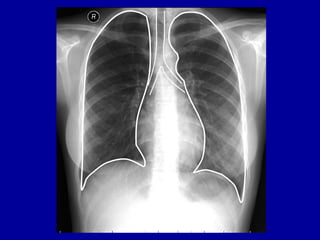

RADIOGRAFIAS DO TÓRAX

• MÉTODO BARATO

• DISPONIBILIDADE

• FACILIDADE PARA REALIZAÇÃO

• RADIOGRAFIAS + CORRELAÇÃO CLÍNICA =

SUFICIENTE PARA A TOMADA DE DECISÕES NA

MAIOR PARTE DOS CASOS DE DOENÇAS

PULMONARES.